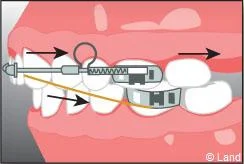

Il s’agit d’un appareil multi-attaches appelé communément « bagues ». Il permet de déplacer très précisément chaque dent. Chaque dent est équipée d’une attache appelée « bracket ». Les dents vont être mobilisées par l’utilisation de fil métallique dont l’alliage, la section, la forme sont déterminés par les différentes étapes du traitement. Ils seront insérés dans les attaches par le biais de ligatures élastiques, métalliques ou d’un mini-clip. Les « brackets » utilisés chez les adolescents sont la plupart du temps métalliques mais ils peuvent être remplacés avantageusement par des éléments transparents ou de la couleur des dents.

Ils sont associés aux bagues et peuvent venir compléter et renforcer l’efficacité de l’appareillage fixe. Il existe des élastiques ou de ressorts qui peuvent aider au déplacement des dents en complément du fil, en servant de guide et des forces extra-orales portées la nuit qui agissent sur des secteurs osseux plus étendus.